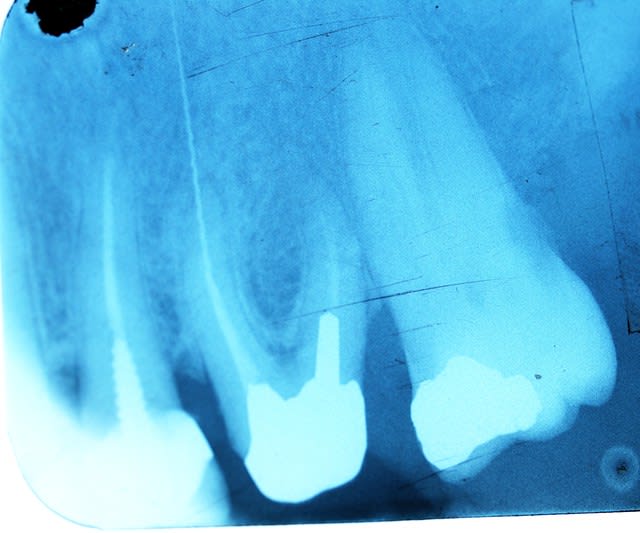

1/3 d endo

1/3 d inlay-core

un petit 1/3 d implanto (a aiguille)

un gros 1/3 de dépassement

18 ans de recul sur cette caguade et rien a signaler .

ben des degats il n y en a pas eu et il n'y en a toujours pas 18 ans apres . chance.

Tu as posé la digue ? il ne semble pas y avoir de problème "péri-implantaire" après 18 ans. Chapeau !

" Tu as posé la digue ? il ne semble pas y avoir de problème péri-implantaire"

après 18 ans. Chapeau ! "

Non non pas de digue .mais j avais deja fait l endo la seance d avant que celle de la mise en broche.

pourquoi veux tu une peri-implantite ?:

+aucune communication avec le milieu exterieur

+lime fine donc pas d echauffement

+ pas de rigidité occlusale

en toute logique ça ne sent pas l embrouille

en fait la séance d après l endo ,je prend une radio et je trouvais l'obturation un poil courte.

Je tiens à preciser que lorsque j'ai ouvert le post et regardé la radio ma première reaction a été de dire "certes c'est deconner mais elle a l’air d'aller bien cette dent", confirmé par la suite de ma lecture, 18 ans et ras.